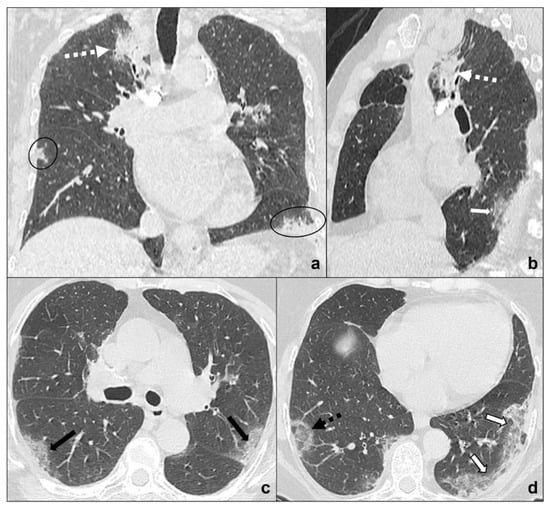

- evidence of coexisting solid/subsolid lung cancer or systemic known cancer;

- bilateral involvement with a random distribution in case of hematogenous spread or with spread thought airspace (STAS);

- ground-glass opacities do not follow COVID-19 phases and are generally asymptomatic in early phases;

- growing despite antibiotics and anti-inflammatory therapies;

- pleural effusions;

- mediastinal lymphadenomegalies.

- evidence of coexisting solid/subsolid cancer;

- unilateral involvement, which is homolateral to lung cancer;

- crazy paving pattern is typical, but does not coexist, follow, or precede

- ground-glass opacities and consolidations, that are typical, respectively, of stage one and three of COVID-19 pneumonia;